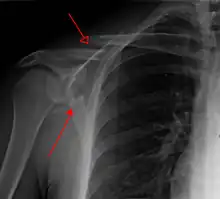

Most fractures of the scapula can be seen on a chest X-ray; however, they may be missed during examination of the film.[1] Serious associated injuries may distract from the scapular injury,[4] and diagnosis is often delayed.[3] Computed tomography may also be used.[1] Scapular fractures can be detected in the standard chest and shoulder radiographs that are given to patients who have had significant physical trauma, but much of the scapula is hidden by the ribs on standard chest X-rays.[4] Therefore, if scapular injury is suspected, more specific images of the scapular area can be taken.[4]